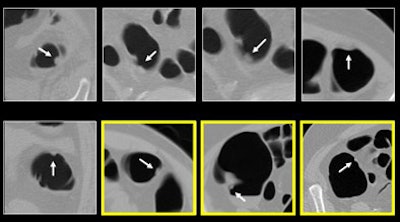

![]() |

| Above, true polyps detected by the CAD algorithm. The three highlighted examples (lower right) were missed by the radiologist. |